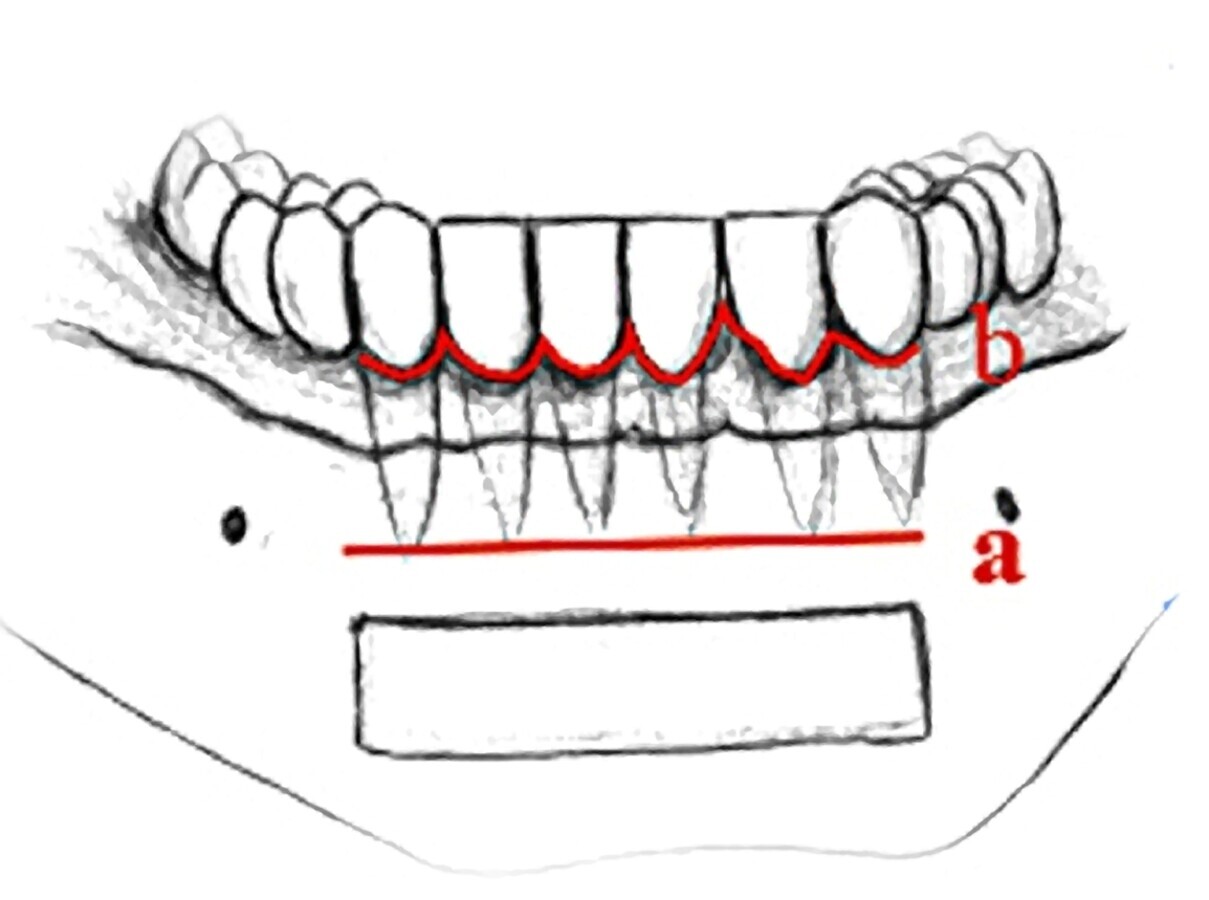

SINFISIS MANDIBULAR

- Anestesia troncular bilateral e infiltrativa

- Tipo de incisión según estado periodontal y nivel de

inserción muscular (extensión limitada a los caninos)

a. Incisión vestibular en la mucosa alveolar: a 3-5 mm de la línea mucogingival.

- Gran iAloinjerto1 nflamación

- Pérdida ósea entorno a los dientes

Aloinjerto1

b. Incisión surcular:

- Vestíbulo poco profundo

-Tensión musculatura mentoniana

- Elevación del colgajo a espesor total

- Osteotomía con fresa redonda a 4 a 5 mm de los ápices dentarios, foramen del mentoniano y borde inferior de la sínfisis delineando el contorno externo del injerto

- Despegamiento del injerto con cincel (no perforar la cortical lingual)

- Conservación del injerto en solución salina

- Relleno del lecho dador con hueso particulado y membrana

- Reposición del colgajo

- Sutura 3/011,21,22